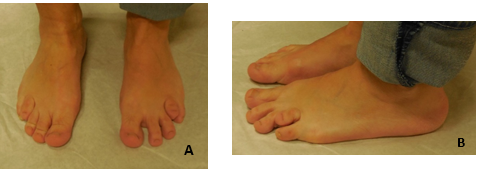

En la radiografía se observa un cuarto metatarsiano hipoplásico bilateral, generando una interrupción clara de la parábola metatarsal; asocia un segundo y tercer metatarsiano largo y un primer metatarso corto. (Figura 8) El metatarsiano hipoplásico no es curvo y no presenta alteraciones en la epífisis distal. Hay una subluxación de la articulación metatarsofalángica.

Figura 8: Radiografía preoperatorio. Se observa alteración de la parábola metatarsal, braquimetatarsia que afecta al cuarto metatarsiano, segundo y tercer metatarsianos largos y subluxación de metatarso falángica.

Luego de un tratamiento conservador fallido se procede a realizar una técnica de alargamiento agudo del cuarto metatarsiano con interposición de un injerto autólogo procedente del tercer metatarsiano, acortamiento del segundo y tercer metatarsiano para restaurar la parábola metatarsal.

Se realiza un abordaje dorsal centrado en el segundo espacio interdigital. Se hace osteotomía transversal, resección de fragmento óseo del segundo y tercer metatarsiano. Se estabilizan los focos con un enclavijado intramedular con alambre de Kirshner.

A nivel del cuarto metatarsiano se efectúa capsulotomía de la metatarsofalángica, zetaplastia del tendón extensor largo y corto del cuarto radio, osteotomía y colocación de injerto con una aguja de Kirshner que se coloca de proximal a distal intrafocal. Saliendo por la planta y de forma retrógrada se coloca en la posición deseada, fijando el injerto; se inmoviliza la articulación metatarsofalángica con Kirshner para prevención de luxación de ésta. Los alambres se retiran a las 6 semanas. (Figura 9 y 10).